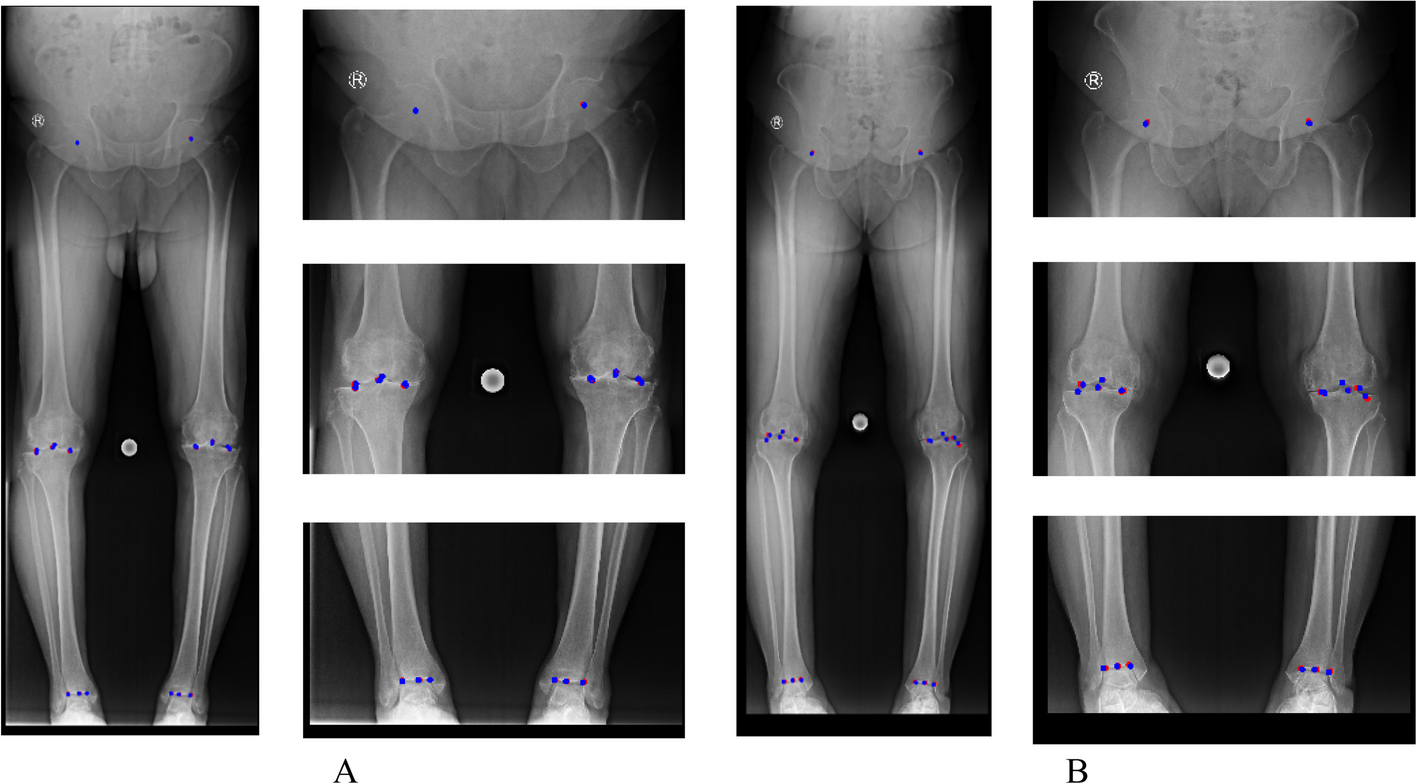

یکی از مشکلات اصلی در بررسی رادیوگرافی اندام تحتانی، شناسایی دقیق نقاط کلیدی استخوانی (landmarks) است. این نقاط شامل مرکز سر استخوان ران، لبههای کندیلهای فمور و تیبیا، و نقاط مفصلی در زانو و مچ پا هستند. هرگونه خطای جزئی در تشخیص این نقاط، میتواند به محاسبه نادرست زوایا منجر شود.

در این پژوهش، تیم تحقیقاتی با همکاری مرکز رادیولوژی و سونوگرافی راد، روشی نوین بر پایه یک ساختار هرمی (Image Pyramid) و شبکه ResNet توسعه دادند. در این روش، تصویر رادیوگرافی با وضوح بالا در چندین مقیاس مختلف پردازش میشود و مدل قادر است نقاط کلیدی استخوانی را به طور دقیق شناسایی کند.

میباشند. در تمامی تصاویر، ۲۶ نقطه کلیدی (۱۳ نقطه برای هر پا) توسط متخصصان رادیولوژی و ارتوپدی نشانهگذاری شده است. این دیتاست نه تنها برای آموزش و آزمایش مدلهای هوش مصنوعی مورد استفاده قرار گرفت، بلکه به صورت عمومی نیز منتشر شده است تا سایر پژوهشگران بتوانند از آن در تحقیقات آینده بهرهمند شوند.